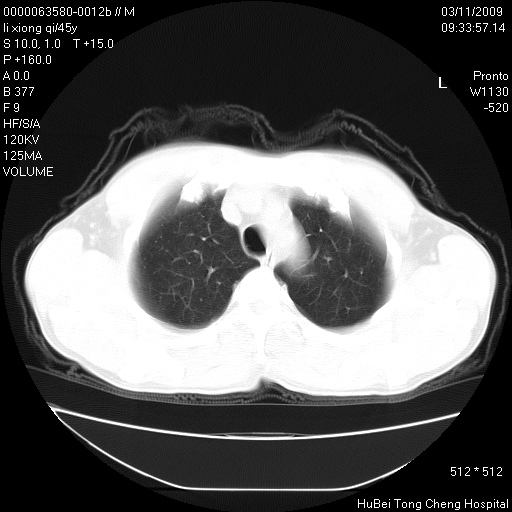

患者 男,45岁。胸痛,咳嗽伴痰中带血1月余。

临床诊断:肺结核?

胸部ct轴位平扫(层厚10mm,螺距1.5,重建间隔10mm),图像如下:

考虑肝癌肺转移